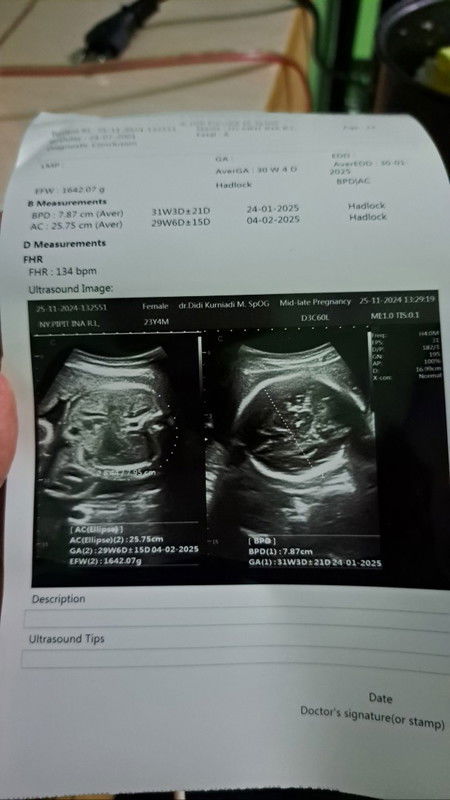

Hallo mom, mau cerita nih dan gimna menurut mom nih? sya kan habis usg tdi trus pengen usg yang 4D pengen yang klihatan muka dedenya krena kan udah 30w jlan 31w dan di hasil usg nya juga trtulis 31w tpi dokter nya ngomong nya baru 6bulan stngah hamil nya jdi gak bisa usg 4d harus dtng 1bulan lagi ktanya, saya bingung mana gak di jelasin apa apa, sya tnya malah gtu jawabnya jdi bete kan, itu benerkan yah mom dari hasil usgnya 31 w? Bukannya kalau 31w itu 7bulan jalan 8bulan yah kan?